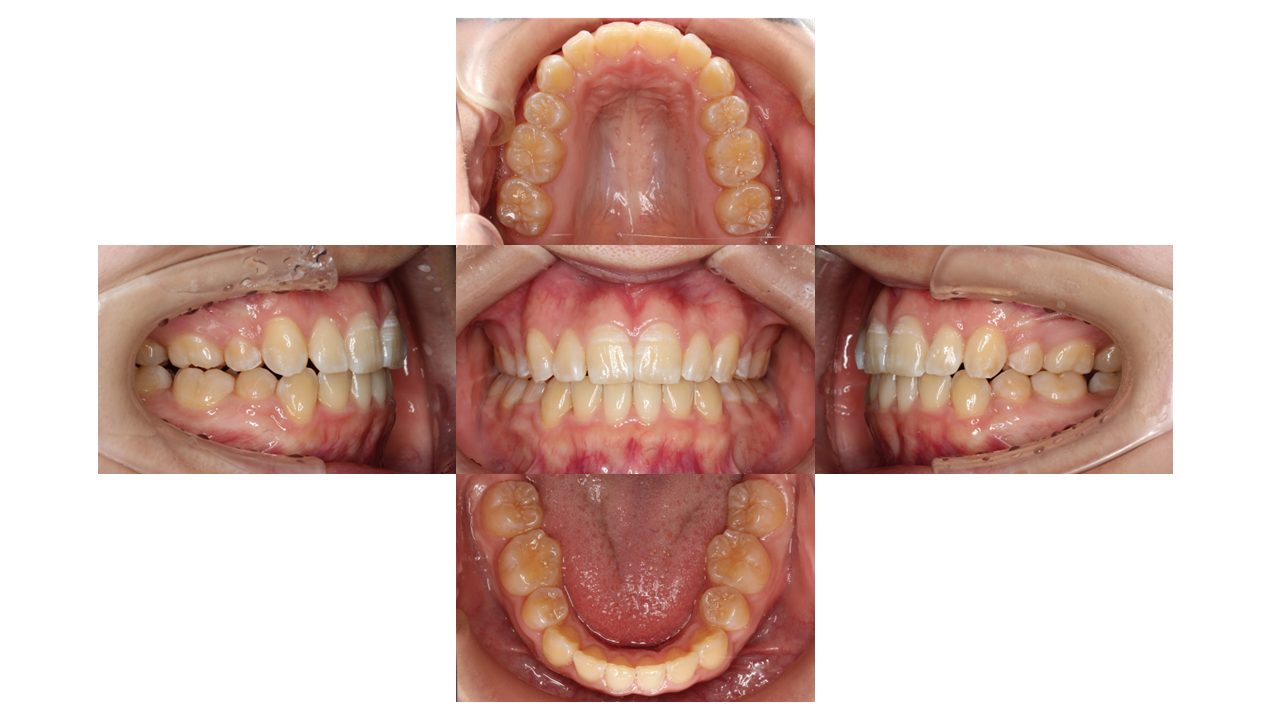

初診時の口腔内の状態です。

前歯の凸凹、特に八重歯にお悩みでご来院されました。